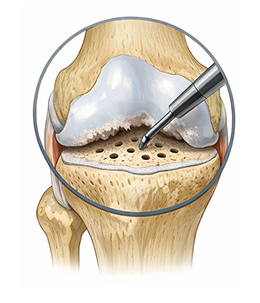

수술적 치료 : 무릎 연골재생술

관절경적 미세천공술(Microfracture)

비교적 작은 연골 결손일 때, 체내 재생을 유도하는 단순하고 부담이 적은 수술입니다.

수술 방법 (어떻게 하는가)

1관절경(내시경)으로 병변 부위 관찰 손상된 연골을 정리

2뼈 표면에 작은 구멍 여러 개를 뚫어 미세천공 시행

3골수에서 재생 세포가 나오도록 유도

4세포들이 굳어져 섬유성 연골(질은 조금 떨어짐)이 새로 채워지는 방식